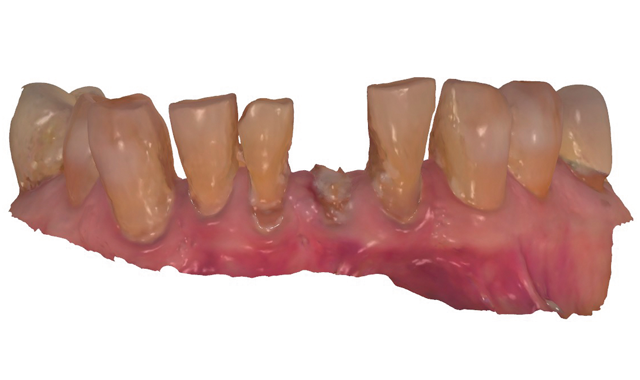

Fig. 1

An 88-year-old man presented for restoration of tooth #25, which was fractured and had been endodontically treated (Fig. 1). A thorough intraoral and radiographic examination was performed, which revealed damage to the remaining anterior mandibular teeth incurred over the years as a result of scaling and curettage (Fig. 2). This damage to the

Fig. 2

root surface of the lower incisors-which was visible on the radiograph (Fig. 3)-is known as “Riffle-ization.” Described by Dr. Riffle as a technique for removing every last bit of calculus during repeated root scaling, what is now known as “Riffle-izing," ultimately-over the years-changes the shape of the neck of the tooth to resemble an hour glass.

Therefore, based on the clinical and visual evaluation, the preferred treatment would be to restore the fractured #25 with a post and crown and four splinted crowns to restore the anatomy of the four incisors and increase their resistance to both mobility and fracture.